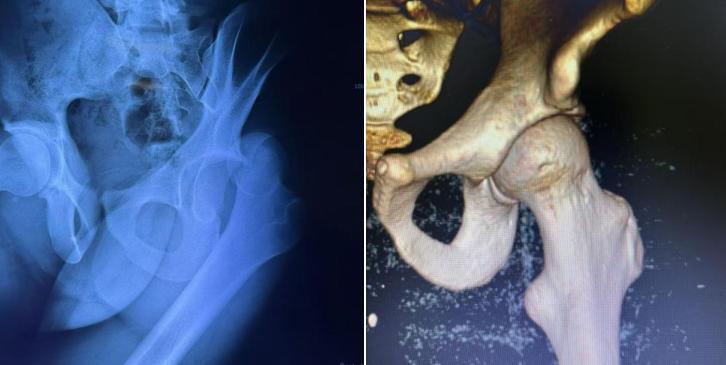

图片

(▲复位前 复位后)